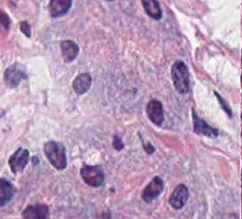

However, nuclei and glands instance segmentation cannot be regarded as a simple task for non experts in pathology labs. Despite being continuous advancements in learning algorithm, nuclei segmentation is still an extremely challenging task because of blurred nuclei boundaries, differences in size and shape highlighted by Vahadane et al. [12], uneven staining, pathological changes on pathological images, morphological abnormalities [13] and substantial color variations described by Rashmi et al. [14]. Similarly, varying morphology of glands at different histological grades, different intrinsic features of glands WSIs poses major challenge during segmentation of instances. Firstly, applying mathematical shape model for instance segmentation gets difficult due to shapes heterogeneity. Figure 2 shows structural variations of nuclei in different organs. Secondly granule filled cytoplasm cause nucleus extrusion to flat shapes as compared to oval or round structures in normal cases mentioned by Yan et al. [15]. Thirdly, cellular matrix variations results in anisochromasia thus resulting in additive noise in background compared to normal intensity gradients.

Improper staining often times result in similarity in nuclei to cytoplasm or background colors thus yielding blurred boundaries [16]. Moreover occurrence of several overlapping nuclei in whole slide images causes further difficulty in objects segmentation. Major challenge in model development is varying types of nuclei e.g nerve cell nuclei are typically triangular in shape [17], while glial and oligodendrocytes nucleus are usually round in appearance but the later one have light rings as, astrocytes have oval shape, endothelial cells are usually slender in structure [18], while malignant tumor cells have irregularly shaped nuclei [19]. Developed model is supposed to be robust enough to detect all these kinds of nuclei without any mislabelling. Digital image quality variation, background clutter, image artifacts are some other extremely important yet least discussed problem in this domain. Nuclei curvature variation also impacts detection since normally in pathology images, nuclei contour points curvature changes smoothly [20]. However, given a single contour having two or more touching or occluding nuclei, results large curvature change at touching points. Already existing automated medical image analysis tool use classical segmentation including active contour models, watershed or thresholding techniques for nuclei instances identification. These tools needs configuration with respect to each data to accurately analyze distinct microscopic modalities including scales and experimental variation, thus leading to an evident requirement of technological domain expertise for accurate algorithm selection and parameters adjustment. Still for proficient ones too, this choice can be daunting, considering that every year numerous papers are published, presenting new research techniques for gland and nucleus instance segmentation. Even after examining under controlled experimental conditions, no single technique can be generalized for segmenting all microscopy images correctly, since classical machine learning algorithms are either sensitive to technical artefacts or often fails in adapting to biological samples heterogeneity. Altogether, this situation yields slows pace of research and at times inhibits research laboratories from adopting newer image analysis technologies owing to the time and expertise required.